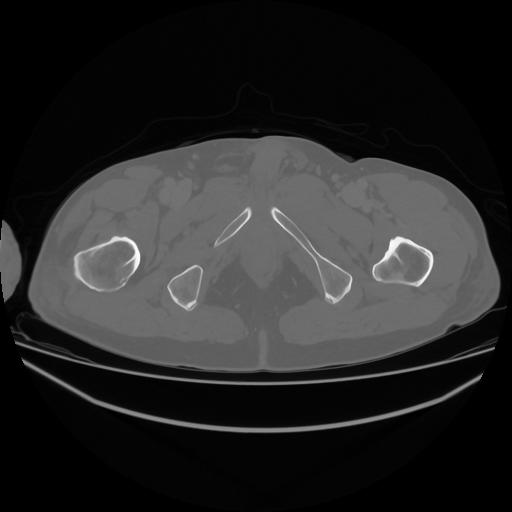

5 CUERPO,CE,Vol,1.0,CUERPO,,